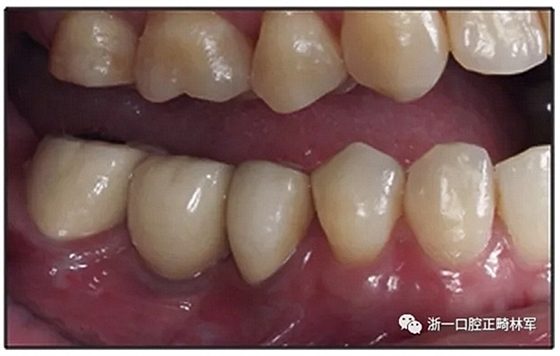

治療結(jié)果

該患者獲得了理想的功能和美觀。

圖3. 治療后面部和口內(nèi)照片